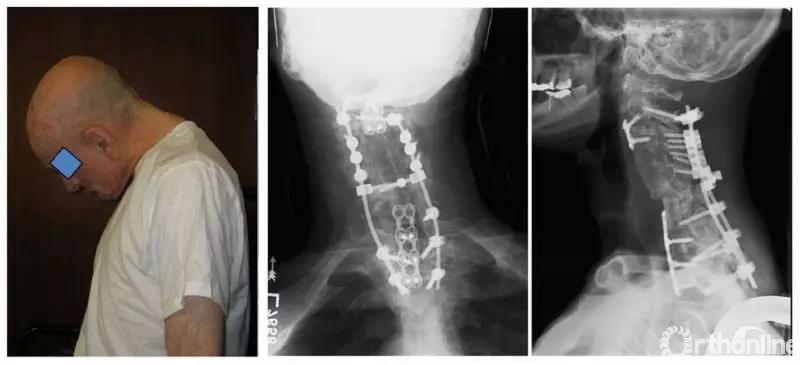

(1)颌触胸(chin-on-chest)畸形(图1),因胸腰椎截骨方式难以纠正其畸形,故而需要通过颈椎截骨恢复平视功能;

图1 术前术后颌触胸(chin-on-chest)畸形通过颈椎截骨恢复平视功能。[1]